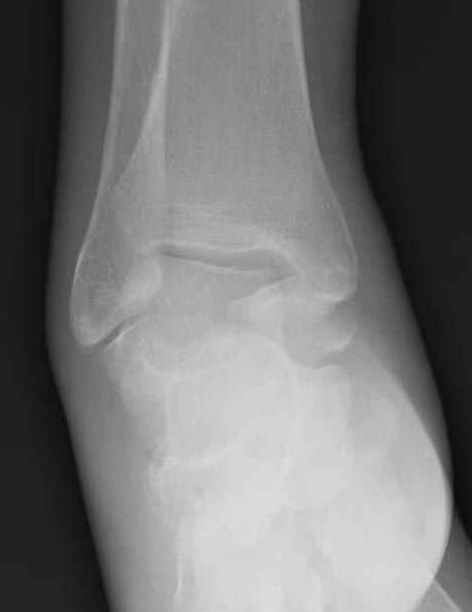

Уважаемые участники русского Ортофорума, поздравляю всех со всеми прошедшими праздниками: Новым годом, Рождеством, Hanukkah, Kwanzaa, желаю участникам всего наилучшего и здоровья.Повреждение таранной кости.Больной 81г автоавария, повреждение таранной кости, здесь снимки. Какие рекомендации?Djoldas Kuldjanov, MDDepartment of Orthopedic SurgerySt. Louis University Medical Center

Вдогонку по поводу перелома таранной кости, больная 81, не страдает диабетом, перелом закрытый, в первый же день поступления ограничились временным наружным фиксатором (как на снимке).

Планировалась открытая фиксация после спадения отека, но больная пожелала лечиться по месту жительству в другом штате..